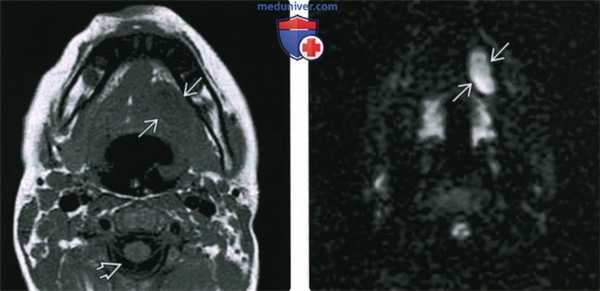

(Слева) МРТ Т1ВИ, аксиальная проекция. Эпидермоидная киста подъязычного пространства. Сигнал от образования минимально гипоинтенсивный относительно скелетных мышц, выраженно гиперинтенсивный относительно ликвора. Такая картина говорит о повышенном содержании белка, что может свидетельствовать в пользу инфицирования или, вероятно, кровоизлияния.

(Справа) MPT DWI, аксиальная проекция, тот же пациент. Гиперинтенсивный сигнал говорящий об ограничении диффузии. Такой вид может быть характерен и для эпидермоидной, и для дермоидной кисты.